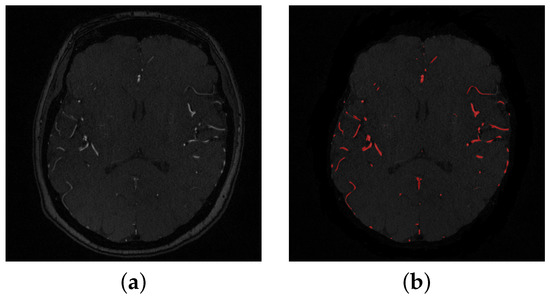

Figure 3. (a) A sample of a 2-D original slice, (b) Segmented slice where detected blood vessels are colored in red.

The segmentation of cerebral vasculature started with a linear combination of discrete Gaussians to estimate the marginal probability density of MRA voxel values for vessels and other brain tissues [18,19]. This results in an initial delineated vasculature that misses some details of the cerebrovasculature such as tiny blood vessels. To enhance the initial segmented vasculature, a 3D adaptive segmentation method was used [20]. This algorithm works by dividing each MRA slice into a set of connected components. A search window of adaptive size was centered around each component in the set and a new separation threshold was calculated as T = μ b + μ o 2 , where μ b is the intensity average of cerebral vessels and μ o is the intensity average of other cerebral tissues. Additionally, a seed-generation refinement procedure was applied to detect potential seeds within regions with a high potential to contain small cerebral vessels that might have been missed in the initial delineated vasculature. Finally, a 3D region growing connected components algorithm was used to obtain the final vasculature. This algorithm achieved 92.23 % Dice similarity coefficient, 94.82 % sensitivity, and 99.0 % specificity. A preprocessing sample is shown in Figure 2, and a segmentation sample output is shown in Figure 3.